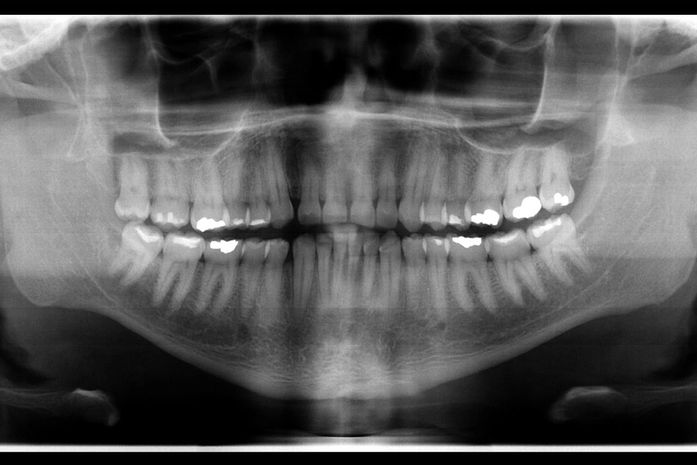

A assessoria de Comunicação do IML afirmou que a partir de documentos solicitados pelo IML e enviados pela então suposta família da vítima, a odontolegista Isabella Lemos confrontou as imagens de antes e depois da morte, e identificou convergências quantitativas, qualitativas e morfológicas suficientes para a identificação do cadáver.

Segundo Isabella Lemos, exames odontológicos realizados durante a vida podem ser essenciais para identificação de cadáveres que chegam ao IML. Os exames disponibilizados pela família continham fotografias extra-orais, intra-orais, radiografia panorâmica e cefalometria, que, de acordo com a perita odontolegista, foram importantes para a identificação da vítima.

“Através desse caso, deu para ressaltar a importância da contribuição dos cirurgiões dentistas com as perícias de identificação odontolegal, já que, por se tratarem de metodologias comparativas, é fundamental que os dentistas que atuam no atendimento preencham adequadamente o prontuário odontológico e que guardem também toda a documentação, como por exemplo os exames radiológicos, modelos em gesso, fotografias do paciente”, aponta Isabella.